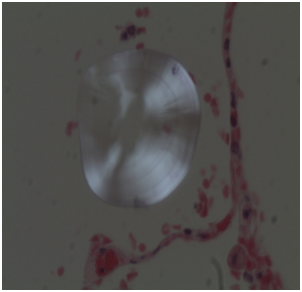

The determination of chemical substances present in the drowning medium could be a complementary tool in the forensic investigation.1,2 Referring to this, both strontium (Sr) and silicon (Si) have proven to be interesting in the diagnosis of drowning (D), in addition to the histological and SEM plankton research in lower airways (Figure 1,Figure 2)(Table 1).

Figure 2 In the upper right, endoalveolar foreign body observed by SEM (case of drowning in freshwater). In the image below, elemental analysis with EDX: more evidence of Si; other organic and inorganic elements.

Histology: Acute emphysema was the prominent observation; edema and hemorrhages were also present.4 In 9 cases (Figures 3-6), exogenous material in the airways, comprehensive of planktonic boli in the lower branches, clearly demonstrable at polarization microscope (and possibly confirmable at SEM’s elemental analysis with EXD). Zoo- and phytoplankton have been better identified in the UV microscope. It is mandatory to differentiate the planktonic material from gastric content, regurgitated and aspirated (Figure 7 & 8).

2. Research of geoplanckton elements, in particular Si (silicon) ,with SEM/EDX.